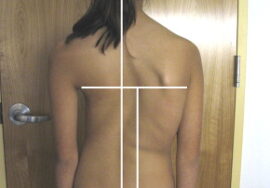

إذا لاحظتِ علامات انحناء في ظهر طفلك، أو لاحظتِ عدم تماثل بين الجانبين، فلا تتردد الأن في استشارة مجانيه من طبيب متخصص.

التشخيص المبكر: مراجعة طبيب العمود الفقري عند ملاحظة أي انحناء مبكر، قبل تفاقم الاعوجاج.

إذا لاحظتِ علامات انحناء في ظهر طفلك، أو لاحظتِ عدم تماثل بين الجانبين، فلا تتردد الأن في استشارة مجانيه من طبيب متخصص.